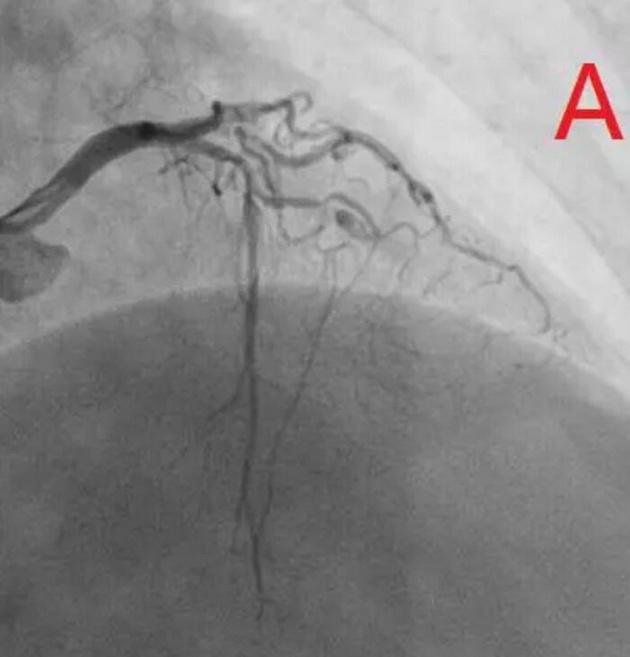

患者为77岁女性,因冠心病进行冠状动脉介入治疗,造影发现冠状动脉前降支不仅闭塞(图A),而且伴有钙化。通过不懈的努力,将闭塞的血管打开,但钙化处球囊无法将病变充分扩张(图B),意味着无法通过植入支架来维持血管管腔。于是采用血管内超声对病变处进行检测,显示病变处存在严重的360度环形钙化(图C、D)。